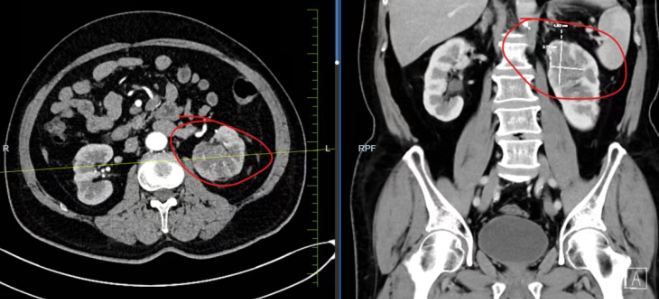

面对这一棘手情况,国文医院泌尿外科团队首先通过腹部增强CT等检查明确肿瘤位置、大小及浸润范围,确立肾盂肿瘤诊断。肾盂肿瘤属于上尿路尿路上皮癌,发病隐匿,根治性肾输尿管切除术是标准治疗术式。